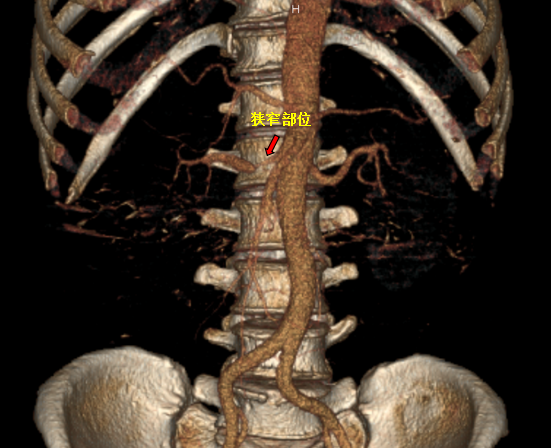

红色标记为支架置入前,右肾动脉明显狭窄

患者于4月9日上午送介入手术室行右肾动脉支架置入术。术中造影显示右肾动脉起始段明显狭窄,狭窄约90%,予置入肾动脉裸支架(7*19mm)后,造影显示右肾动脉狭窄解除,支架扩张良好,右肾灌注恢复。